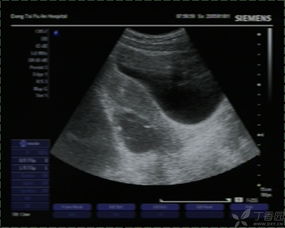

常規(guī)B超檢查是不需要空腹的,因?yàn)樗皇芟罋怏w的影響,常規(guī)B超檢查主要是通過(guò)B超的探測(cè)頭在腹部進(jìn)行探測(cè),從而檢查女性的子宮以及盆腔部位。并且懷孕的女性做B超,一般也是做常規(guī)B超檢查,而不是采取陰道B超檢查,因?yàn)槟軌蜃畲蟮谋Wo(hù)胎兒。

肝膽胰等部位的B超檢查需要空腹,因?yàn)楦文懸任挥谂枨桓共康纳钐?,因此也就特別容易受到消化道氣體的影響,如果不空腹去進(jìn)行檢查就非常容易使結(jié)果產(chǎn)生偏差,從而達(dá)不到檢查的目的。

做B超檢查的時(shí)候是否空腹,主要是看具體是針對(duì)哪一部位的B超檢查,要具體情況具體分析。如果不知道自己做的B超檢查是否要空腹,需要提前就咨詢醫(yī)生,以免耽誤檢查的時(shí)間。